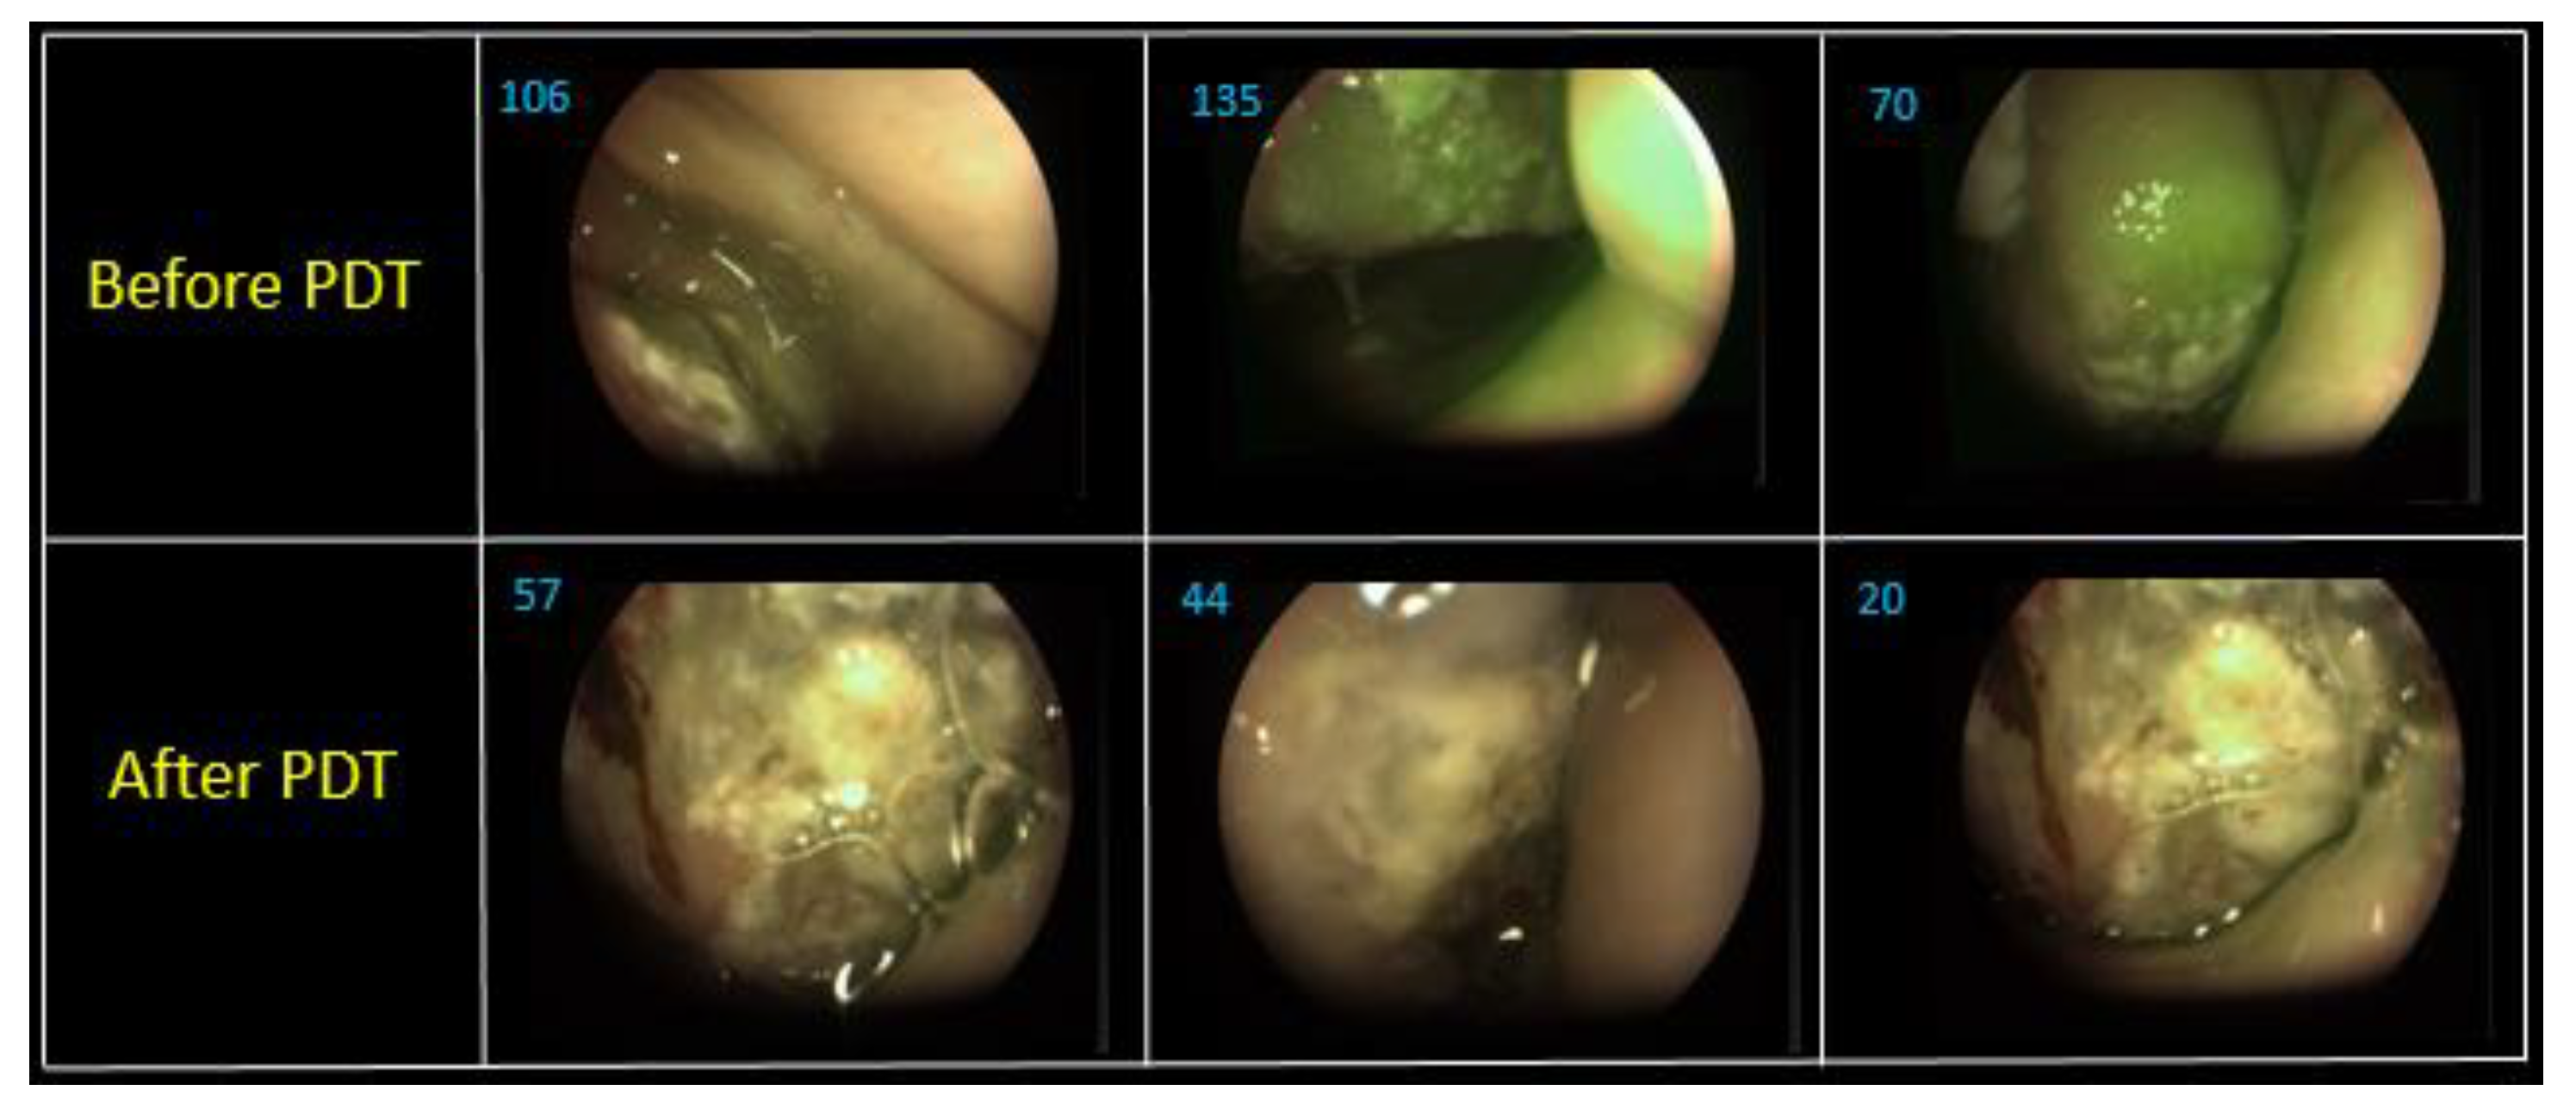

All patients demonstrated the high fluorescence intensity in the area of the malignant neoplasm in comparison with healthy tissue in 2 h after the PS injection. The fluorescent contrast of exogenous fluorophores indicates the selectivity of drug accumulation in pathological foci. The patients felt some discomfort, such as a burning sensation in the area of radiation or pain reactions during the therapy. Lidocaine irrigation of the mucous tissue in the area of pathology contributed to sufficient analgesia for further therapy. PDT on the vocal cords was performed with 22 J/cm2 fluence for the comfortable therapy process. Anamnesis records indicated that 40 years ago this patient had already undergone the removal of benign tumors of the vocal cords. The patient had complaints on hoarseness of voice and dry cough in March 2019. The diagnosis revealed multiple formations on the vocal cords and squamous cell cancer was detected after histological research. Considering the patient’s age (94 years old) and the concomitant disease, the Oncological Council recommended to conduct PDT. Evaluation of the treatment’s effectiveness in the patient with malignant neoplasm of the vocal cords was performed 7 days after the PDT procedure. The results showed the tumor regression after the first PDT session (Figure 4). The repeated diagnosis of the patient vocal cords was performed in 1.5 months, which did not reveal a tumor recurrence.

Figure 4. The visible images of vocal cord: (a) before PDT; (b) in week after PDT.